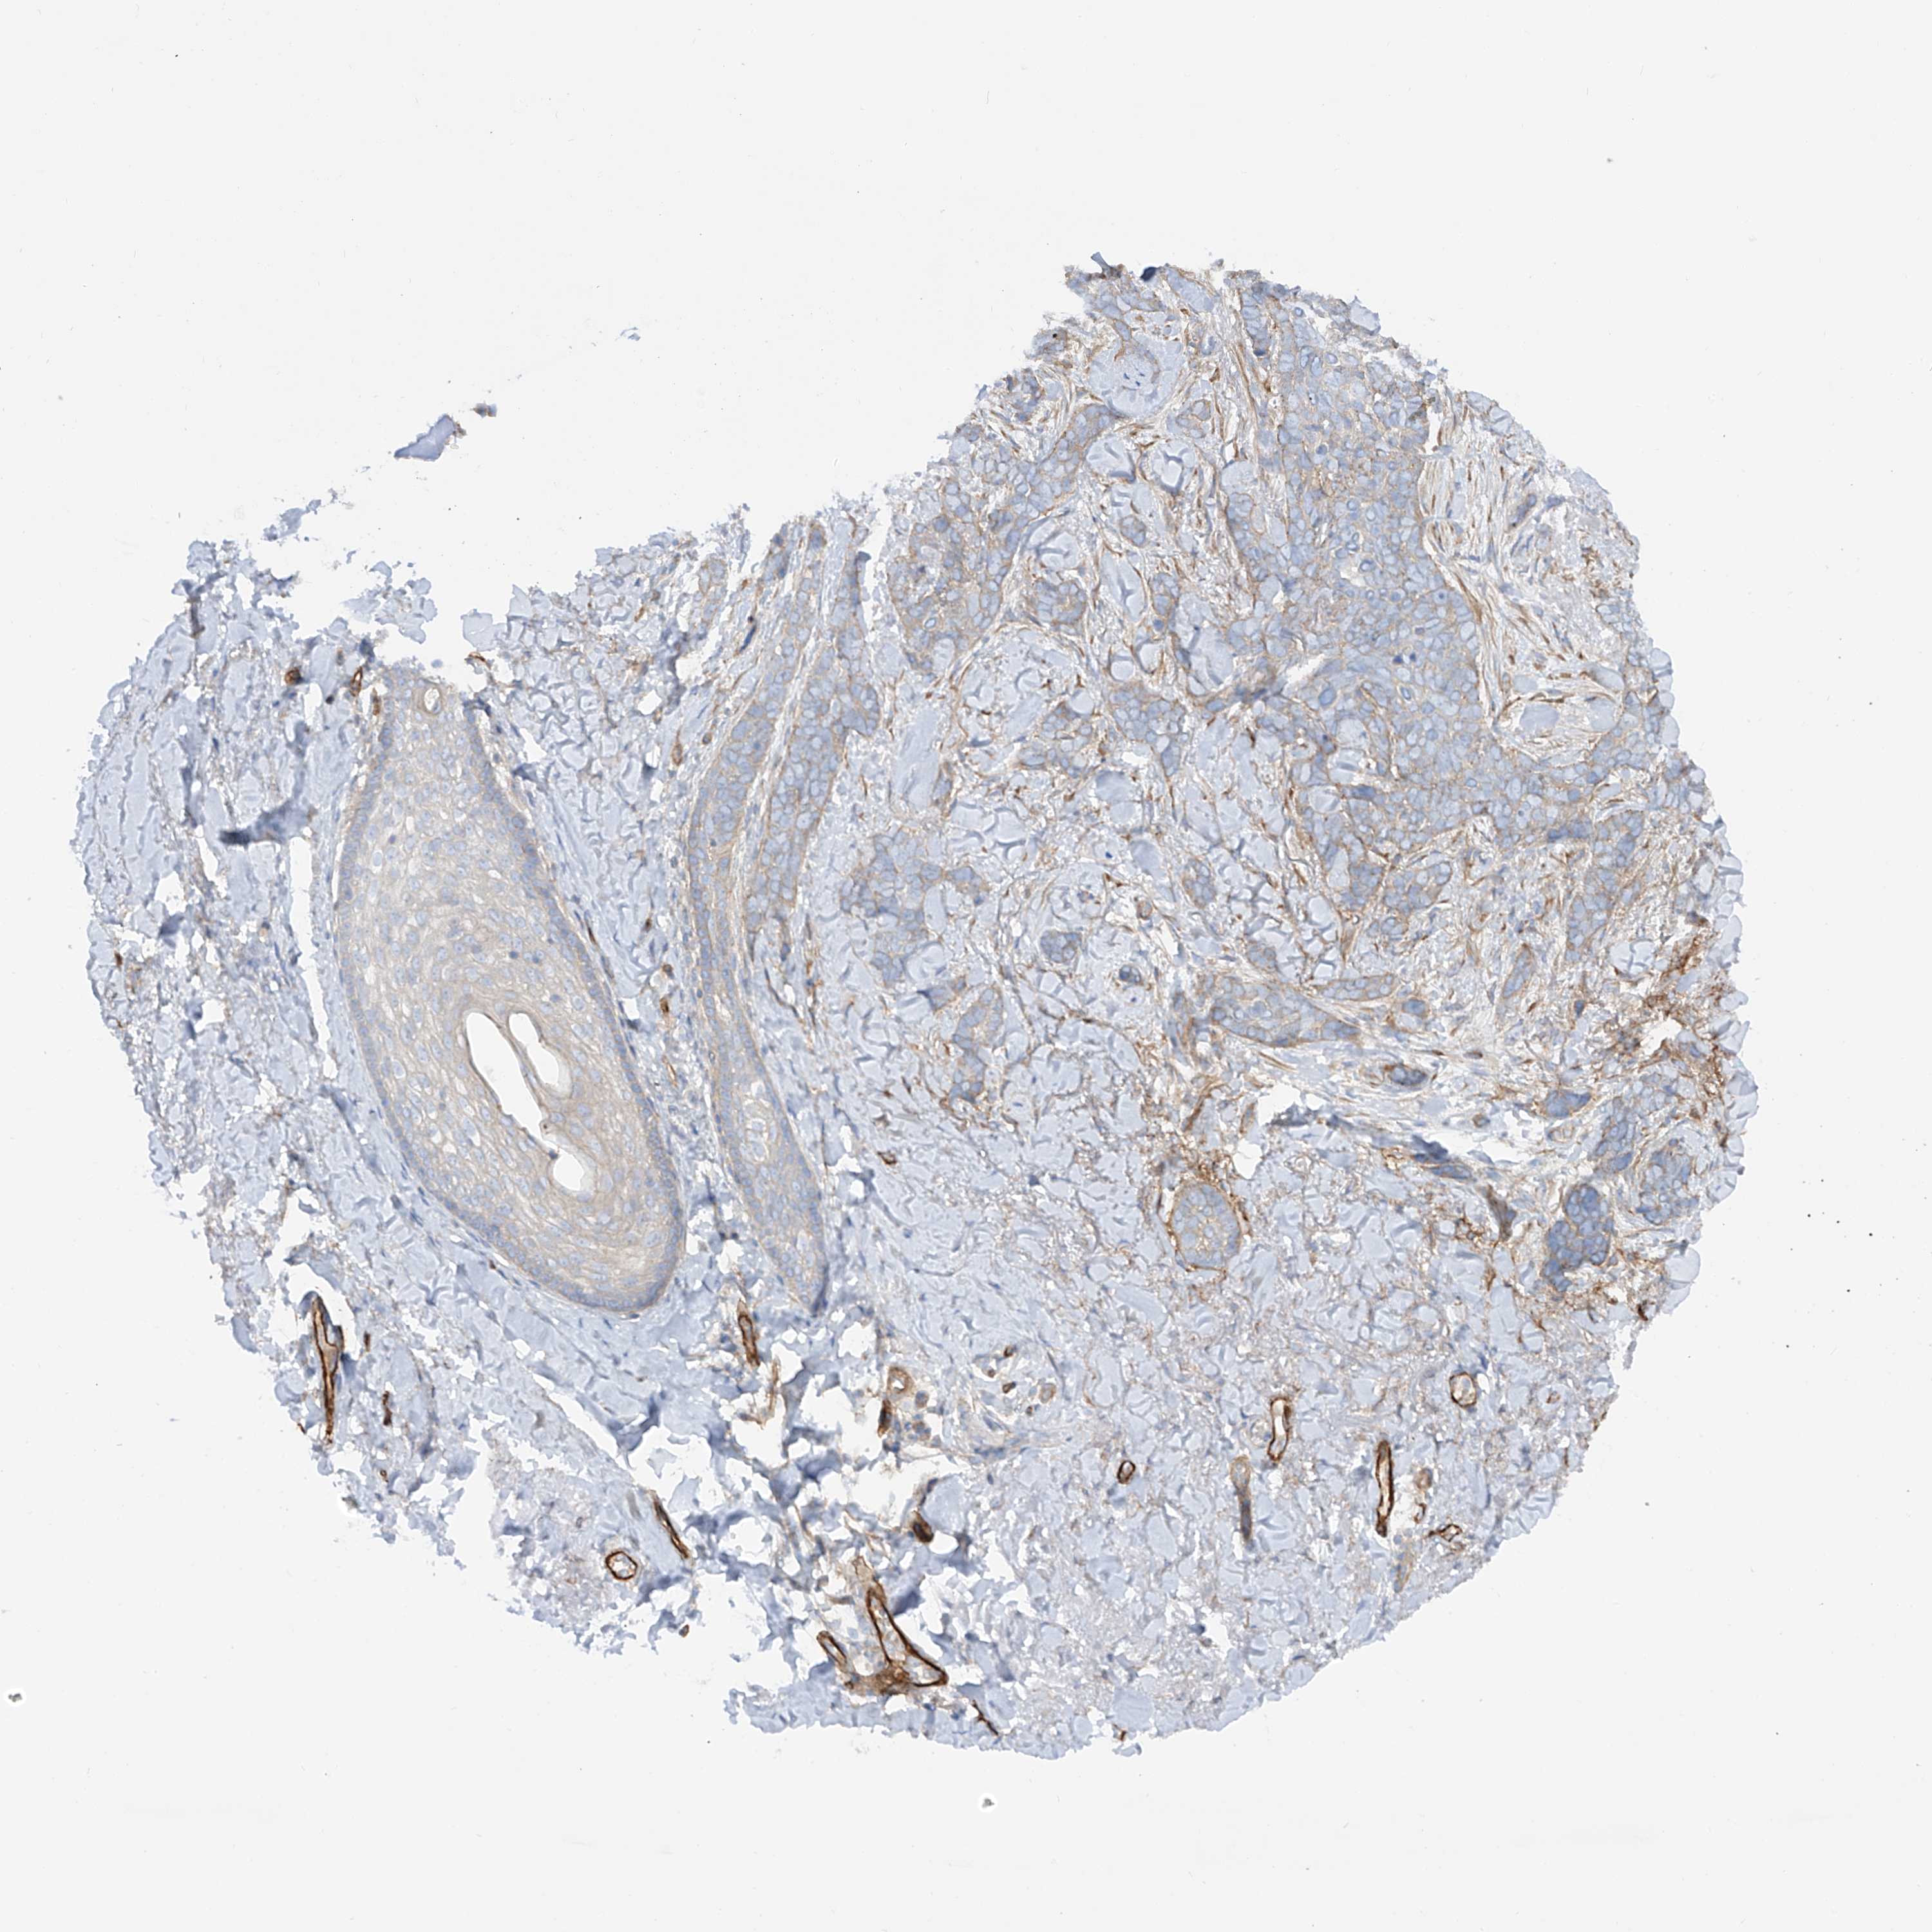

Basal cell and squamous cell cancer

SKIN CANCER - Protein expressioni

A mouse-over function shows sample information and annotation data. Click on an image to view it in a full screen mode. Samples can be filtered based on level of antibody staining by selecting one or several of the following categories: high, medium, low and not detected. The assay and annotation is described here.

Antibody stainingi

Antibody staining in the annotated cell types in the current human tissue is reported as not detected, low, medium, or high, based on conventional immunohistochemistry profiling in selected tissues. This score is based on the combination of the staining intensity and fraction of stained cells.

Each image is clickable and will lead to virtual microscopy that enables deeper exploration of all samples and also displays staining intensity scores, fraction scores and subcellular localization as well as patient and tissue information for each sample.

Antibody HPA029053

Antibody HPA029055

Staining

High

Medium

Low

Not detected

Intensity

Strong

Moderate

Weak

Negative

Quantity

>75%

75%-25%

<25%

None

Location

Nuclear

Cytoplasmic/membranous

Cytoplasmic/membranous,nuclear

Squamous cell carcinoma, NOS

Squamous cell carcinoma, metastatic, NOS